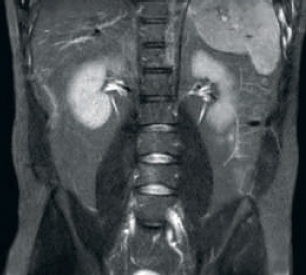

Result: Improved SNR and image resolution